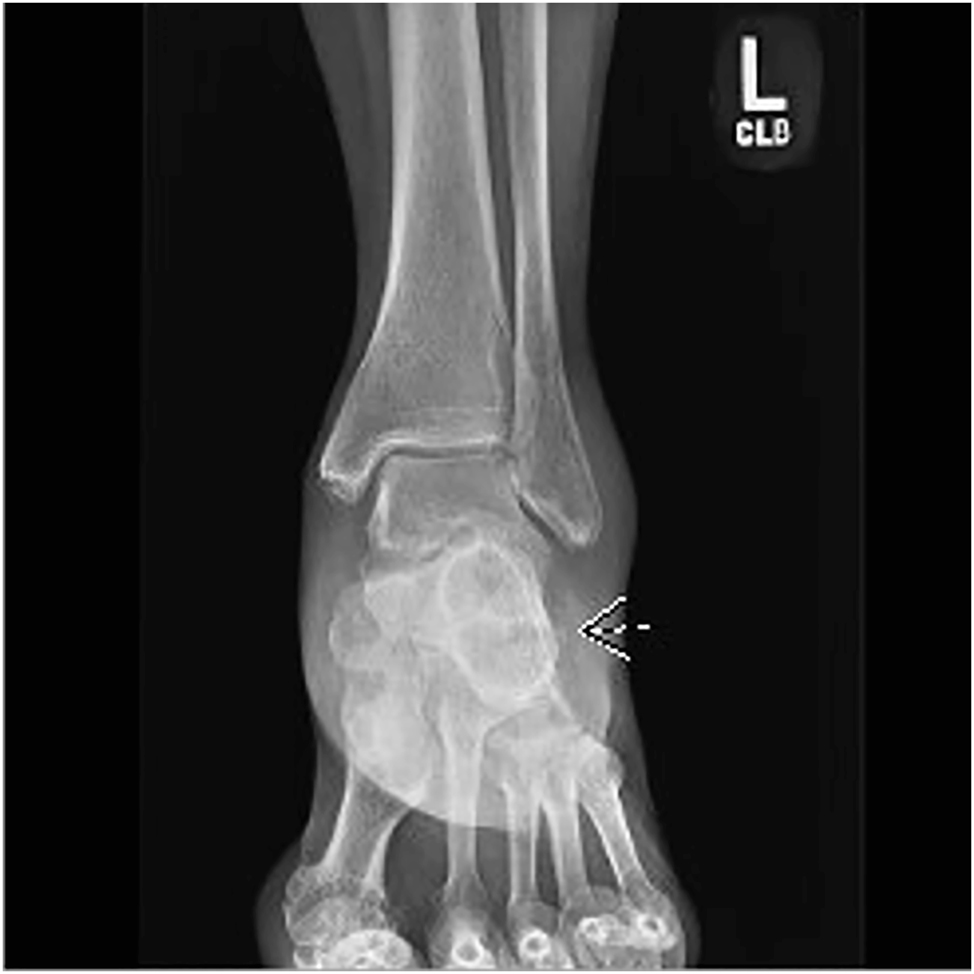

The anteroposterior X-ray of the left foot showing a nondisplaced avulsion fracture of the lateral calcaneus.

A 75-year-old woman presented to the emergency department in January 2023 with pain and swelling of the lateral left ankle after an inversion injury 1 week earlier. She underwent X-rays of the left foot, and she was diagnosed with a small, nondisplaced avulsion fracture of the lateral calcaneus as well as a large Haglund deformity of the calcaneus (Figures 1 and 2). The patient noted that she had a history of ankle pain due to a Haglund deformity, a bony prominence found on the superior posterior aspect of the calcaneus [1], [2], [3]. The deformity caused pain that worsened with ambulation. The pain also worsened when wearing sling-back shoes. It became too painful for her to walk, so she had surgery approximately 50 years ago to partially remove the deformity and lift the Achilles tendon. Since then, she has been doing well and has not had any heel discomfort.